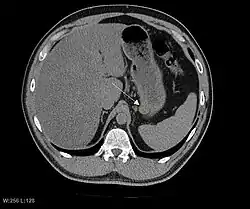

Imaging

The purpose of radiologic imaging is to locate the lesion, evaluate for signs of invasion and detect metastasis. Features of GIST vary depending on tumor size and organ of origin. The diameter can range from a few millimeters to more than 30 cm. Larger tumors usually cause symptoms in contrast to those found incidentally which tend to be smaller and have better prognosis.[4][20] Large tumors tend to exhibit malignant behavior but small GISTs may also demonstrate clinically aggressive behavior.[21]

Barium fluoroscopic examinations and CT are commonly used to evaluate the patient with abdominal complaints. Barium swallow images show abnormalities in 80% of GIST cases.[21] However, some GISTs may be located entirely outside the lumen of the bowel and will not be appreciated with a barium swallow. Even in cases when the barium swallow is abnormal, an MRI or CT scan must follow since it is impossible to evaluate abdominal cavities and other abdominal organs with a barium swallow alone. In a CT scan, abnormalities may be seen in 87% of patients and it should be made with both oral and intravenous contrast.[21] Among imaging studies, MRI has the best tissue contrast, which aids in the identification of masses within the GI tract (intramural masses). Intravenous contrast material is needed to evaluate lesion vascularity.

Preferred imaging modalities in the evaluation of GISTs are CT and MRI,[23]: 20–21 and, in selected situations, endoscopic ultrasound. CT advantages include its ability to demonstrate evidence of nearby organ invasion, ascites, and metastases. The ability of an MRI to produce images in multiple planes is helpful in determining the bowel as the organ of origin (which is difficult when the tumor is very large), facilitating diagnosis.

.jpg)

Since GISTs arise from the bowel layer called muscularis propria (which is deeper to the mucosa and submucosa from a luminal perspective), small GIST imaging usually suggest a submucosal process or a mass within the bowel wall. In barium swallow studies, these GISTs most commonly present with smooth borders forming right or obtuse angles with the nearby bowel wall, as seen with any other intramural mass. The mucosal surface is usually intact except for areas of ulceration, which are generally present in 50% of GISTs. Ulcerations fill with barium causing a bull's eye or target lesion appearance. In contrast-enhanced CT, small GISTs are seen as smooth, sharply defined intramural masses with homogeneous attenuation.

Large GISTs

As the tumor grows it may project outside the bowel (exophytic growth) and/or inside the bowel (intraluminal growth), but they most commonly grow exophytically such that the bulk of the tumor projects into the abdominal cavity. If the tumor outstrips its blood supply, it can necrose internally, creating a central fluid-filled cavity with bleeding and cavitations that can eventually ulcerate and communicate into the lumen of the bowel. In that case, barium swallow may show an air, air-fluid levels or oral contrast media accumulation within these areas.[21][25] Mucosal ulcerations may also be present. In contrast-enhanced CT images, large GISTs appear as heterogeneous masses due to areas of living tumor cells surrounding bleeding, necrosis or cysts, which is radiographically seen as a peripheral enhancement pattern with a low attenuation center.[20] In MRI studies, the degree of necrosis and bleeding affects the signal intensity pattern. Areas of bleeding within the tumor will vary its signal intensity depending on how long ago the bleeding occurred. The solid portions of the tumor are typically low signal intensity on T1-weighted images, are high signal intensity on T2-weighted images and enhanced after administration of gadolinium. Signal-intensity voids are present if there is gas within areas of necrotic tumor.[22][26][27]

Features of malignancy

Malignancy is characterized by local invasion and metastases, usually to the liver, omentum and peritoneum. However, cases of metastases to bone, pleura, lungs and retroperitoneum have been seen. In distinction to gastric adenocarcinoma or gastric/small bowel lymphoma, malignant lymphadenopathy (swollen lymph nodes) is uncommon (<10%) and thus imaging usually shows absence of lymph node enlargement.[20] If metastases are not present, other radiologic features suggesting malignancy include: size (>5 cm), heterogeneous enhancement after contrast administration, and ulcerations.[4][20][28] Also, overtly malignant behavior (in distinction to malignant potential of lesser degree) is less commonly seen in gastric tumors, with a ratio of behaviorally benign to overtly malignant of 3-5:1.[4] Even if radiographic malignant features are present, these findings may also represent other tumors and definitive diagnosis must be made immunochemically.